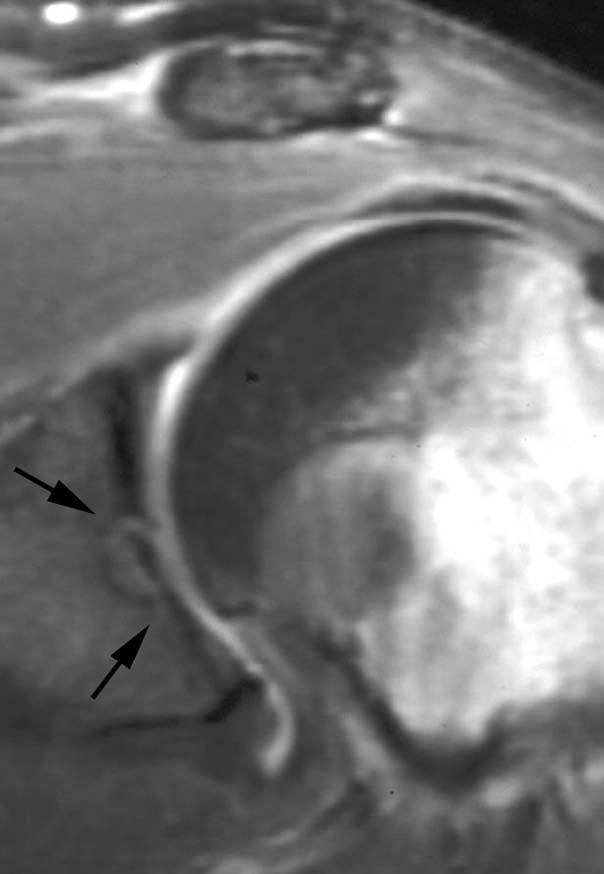

Lesión de Perthes

La lesión de Perthes es similar a la de Bankart, con la excepción de que no existe rotura capsuloperióstica, aunque el periostio puede estar separado del borde anterior del margen glenoideo (fig. 10). Esta lesión puede ser difícil de visualizar, incluso con artrorresonancia, a menos que se obtengan imágenes con la posición de abducción y rotación externa (ABER). En un estudio de 10 casos, verificados quirúrgicamente, Wisher et al17 comprobaron que el 50% de las lesiones de Perthes sólo podían visualizarse en la posición de ABER.

Fig. 10.--Lesión de Perthes. Artrorresonancia T1 con saturación grasa en posición ABER (abducción y rotación externa), donde se observa un arrancamiento parcial del labio glenoideo (flecha) con conservación de la unión capsuloperióstica.